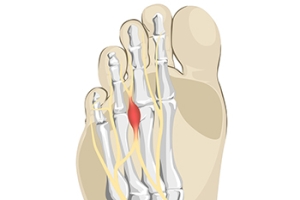

Pain From Morton’s Neuroma

A Morton’s neuroma refers to thickening of nerve tissue at the base of the 3rd or 4th toe. While the precise cause of this condition is unknown, it is thought to form from pressure, irritation, or injury of nerves leading to the toes. This condition can cause one to feel like there is a lump or knot near the ball of the foot, like they are walking on a pebble, or wearing socks that have become bunched up. There can be an achy, sharp, or burning pain in the ball of the foot, or tingling, numbness, or cramping in the forefoot or toes. A Morton’s neuroma can become swollen and painful. One can develop a Morton’s neuroma from wearing shoes that are too narrow where the toes are squeezed together or high-heeled shoes where the body weight is forced onto the ball of the foot. Non-invasive treatments for Morton’s neuroma include wearing properly fitted shoes, with heels less than two inches in height, wide toe boxes, and thick soles, using padding in shoes to take the pressure off the nerve, or taping the feet to redistribute body weight and ease inflammation. Medication and injections can also help relieve pain and pressure of this ailment. Custom orthotics can be made to provide support if one has an abnormal foot structure, such as flat feet or overlapping toes causing the condition. Surgery can be performed if a Morton’s neuroma becomes large or fails to be relieved with more conservative treatment options. Left untreated, a Morton’s neuroma can become worse. For this reason, it is suggested that you visit a podiatrist for a proper diagnosis and treatment that fits the severity of your specific foot problem.

Morton’s neuroma is a very uncomfortable condition to live with. If you think you have Morton’s neuroma, contact one of our podiatrists of Lexington Foot and Ankle Center, PSC. Our doctors will attend to all of your foot care needs and answer any of your related questions.

Morton’s Neuroma

Morton's neuroma is a painful foot condition that commonly affects the areas between the second and third or third and fourth toe, although other areas of the foot are also susceptible. Morton’s neuroma is caused by an inflamed nerve in the foot that is being squeezed and aggravated by surrounding bones.

What Increases the Chances of Having Morton’s Neuroma?

- Ill-fitting high heels or shoes that add pressure to the toe or foot

- Jogging, running or any sport that involves constant impact to the foot

- Flat feet, bunions, and any other foot deformities

Morton’s neuroma is a very treatable condition. Orthotics and shoe inserts can often be used to alleviate the pain on the forefront of the feet. In more severe cases, corticosteroids can also be prescribed. In order to figure out the best treatment for your neuroma, it’s recommended to seek the care of a podiatrist who can diagnose your condition and provide different treatment options.

What is Morton's Neuroma?

Morton’s neuroma, (also referred to as Morton’s metatarsalgia, Morton’s neuralgia, plantar neuroma or intermetatarsal neuroma) is a condition that is caused when the tissue around one of the nerves between your toes begins to thicken. This thickening can result in pain in the ball of the foot. Fortunately, the condition itself is not cancerous.

Morton’s neuroma affects women more often than men with a ratio of 4:1. It tends to target women between the age of 50 and 60, but it can occur in people of all ages. There are some risk factors that may put you at a slightly higher risk of developing the condition. People who often wear narrow or high-heeled shoes are often found to be linked to Morton’s neuroma. Additionally, activities such as running or jogging can put an enormous amount of pressure on the ligament and cause the nerve to thicken.

There usually aren’t any outward symptoms of this condition. A person who has Morton’s neuroma may feel as if they are standing on a pebble in their shoe. They may also feel a tingling or numbness in the toes as well as a burning pain in the ball of their foot that may radiate to their toes.

In order to properly diagnose you, the doctor will press on your foot to feel for a mass or tender spot. He may also do a series of tests such as x-rays, an ultrasound, or an MRI. X-rays are usually done to rule out any other causes for your foot pain such as a stress fracture. Ultrasounds are used to reveal soft tissue abnormalities that may exist, such as neuromas. Your podiatrist may want to use an MRI in order to visualize your soft tissues.

There are three main options for treatment of Morton’s neuroma: Injections, decompression surgery, and removal of the nerve. Injections of steroids into the painful area have been proven to help those with Morton’s neuroma. Decompression surgery has been shown to relieve pressure on the affected nerve by cutting nearby structures such as the ligaments in the foot. Another treatment option would be to surgically remove the growth to provide pain relief.

If you suspect that you have Morton’s neuroma you should make an appointment with your podiatrist right away. You shouldn’t ignore any foot pain that lasts longer than a few days, especially if the pain does not improve.